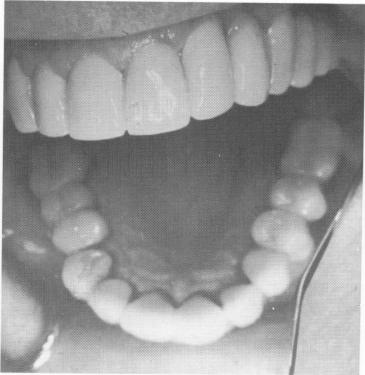

This patient's teeth were unattractive and in poor condition (Fig. 11-50). His remaining mandibular teeth were prepared for full crown restorations. After the castings were fitted over the abutment teeth and all occlusal adjustments made, local anesthesia was given, one side at a time. The first blade was inserted in the right mandibular molar area (Fig. 11-51) and the second in the left (Fig. 11-52). The sites were then sutured closed (Fig. 11-53), and a prefabricated temporary splint lined with a soft tissue conditioner was placed over the abutment teeth and implant posts (Fig. 11-54).

Fig. 11-52. Both mandibular implants are seated.